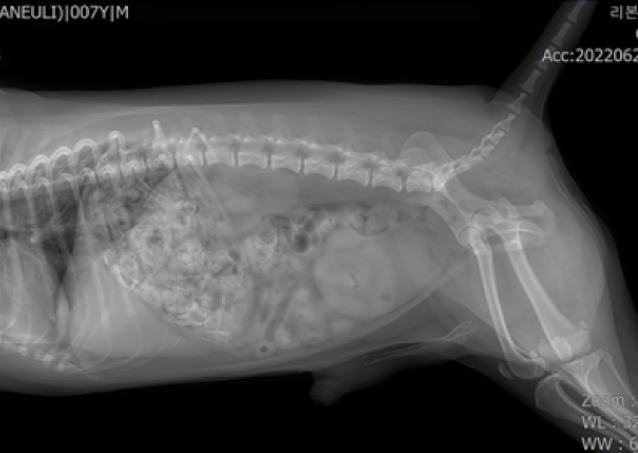

입원 4시간 후 촬영한 x-ray 사진에서 위 내용물의 변화가 없었으나 다행히 안락동동물병원 리본동물의료센터는 이 아이가 소화제를 먹고 오전 8시경 찍은 x-ray에서 내용물이 조금씩 내려가는 것을 확인할 수 있었습니다.

하지만 소화기관을 통해서 내려가는 와중에도 손상을 일으킬 수 있으므로 퇴원 후에도 변 상태, 구토, 설사 등 임상증상 발생 여부 등을 모니터링하여야 합니다.